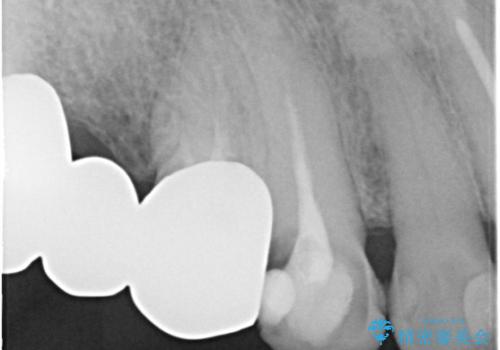

下顎の両側の奥歯が欠損しており、入れ歯をお持ちでしたが、うまく咬めずにほとんど使用していない状態でした。

上顎は全体的にクラウンの入れ替えと、下顎はインプラントの提案もしましたが、希望されなかったのでノンクラスプデンチャーの製作をする治療計画としました。

奥歯が欠損しており、上下の前歯が強く咬合する可能性があったので、上顎前歯の裏側は金属のものにしました。